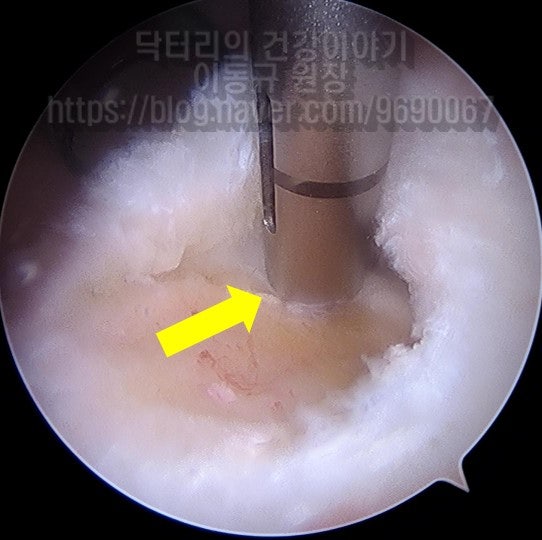

이 환자의 경우 나이가 비교적 젊음에도 불구하고 힘줄의 상태가 매우 좋지 않았습니다. 아마 수년간 통증주사(아마도 스테로이드)만 맞고 팔을 계속 사용하면서 회전근개 손상은 점점 진행되고 퇴행성 변화가 가속화 된 것으로 사료됩니다. 수술 후 6주에 MRI 검사를 시행하였습니다.